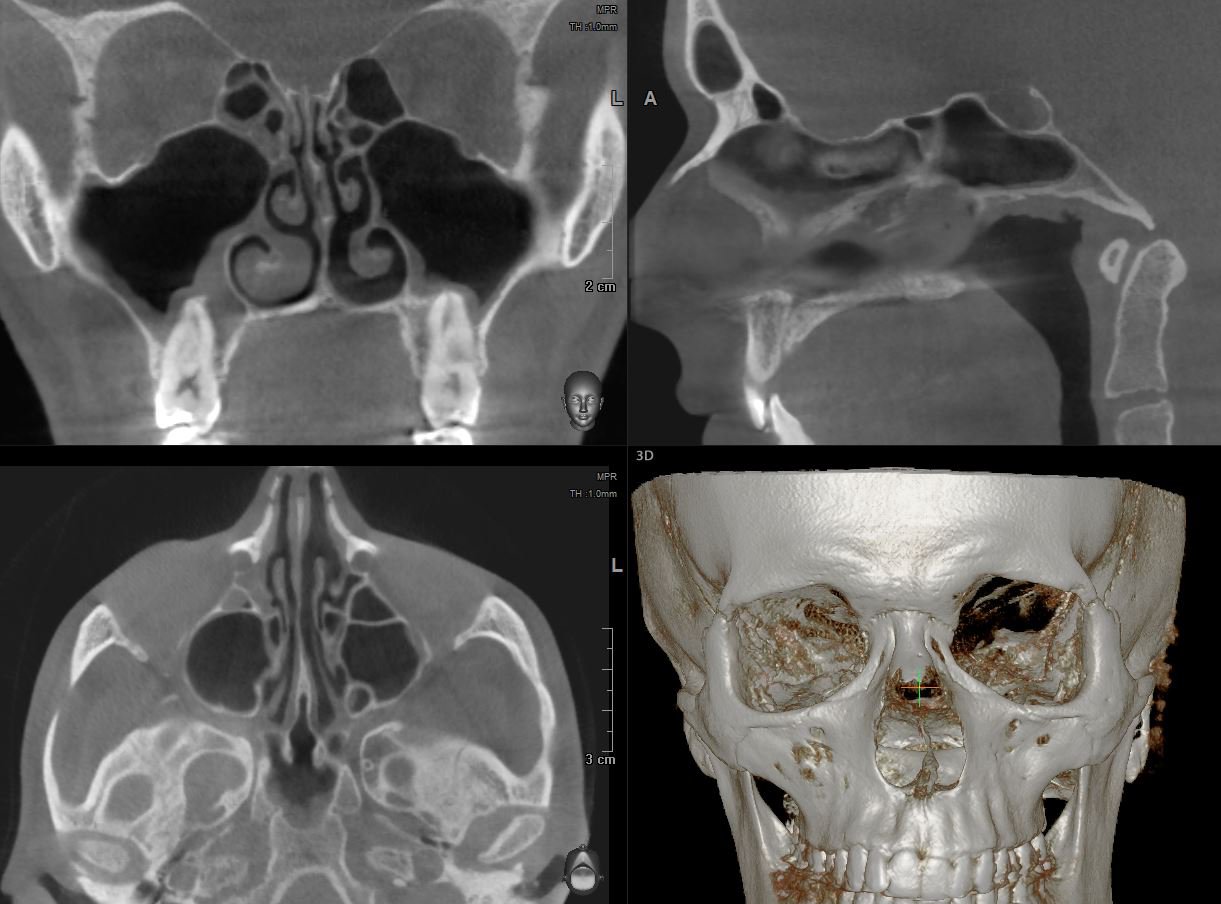

КТ-снимки хронического этмоидита: подробная визуализация

Раздел: Фотодневник открытий